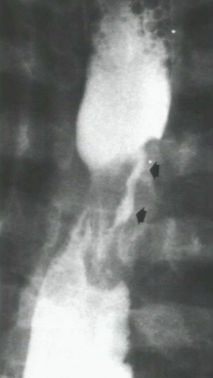

What is your diagnosis?

There is a mass blocking flow of the barium during the swallow indicating a filling defect. This is a large squamous cell carcinoma.